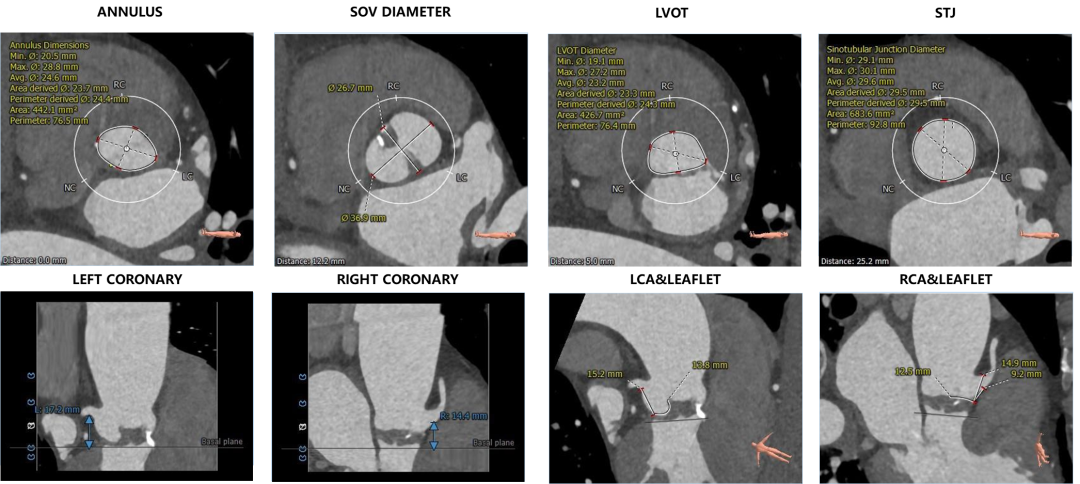

1. 主动脉瓣瓣环周长76.5,平均周长径24.6。

2. Type0型二叶式主动脉瓣,左右冠脉共窦,轻度钙化,钙化主要分布于瓣叶一侧对合缘周围,无冠窦底零星钙化,瓣叶明显增厚。

3. 左右冠开口高度可,切线位右冠窦瓣叶长度略长于瓣叶附着缘到冠脉下开口距离。

4. 横位心,升主扭曲轻度扩张,流出道呈直筒状,主动脉弓宽度及弓部夹角可。

主动脉根部评估

瓣环上解剖结构评估